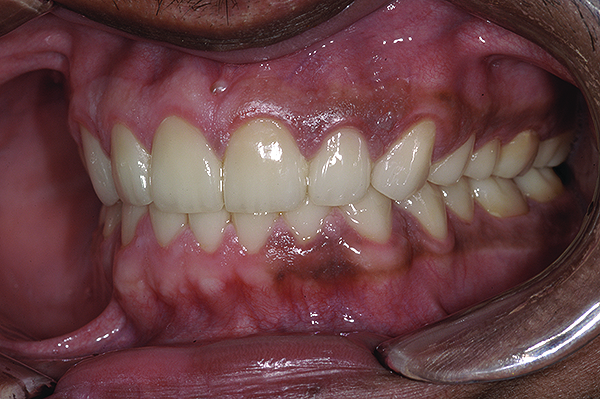

Figure 3. Preoperative 1:2 retracted right lateral view.

Figure 3

Figure 4. Preoperative 1:2 retracted left lateral view.

Figure 4

A thorough clinical examination and analysis were carried out to assess the esthetic and functional problems of the patient (Figure 2 through Figure 7). The medical history was non-contributory, except for mild leukoderma. Temporomandibular joint (TMJ) function was within normal range.

Mounted study casts were used to evaluate occlusion. The relevant findings were as follows2: Facial analysis revealed a canted maxillary occlusal plane and canted dental midline. Dentolabial analysis showed that the maxillary incisors were not adequately visible during repose; it also revealed a reverse smile line, as well as a wide smile showing 12 teeth. Results from the phonetic analysis were that “F” and “V” sounds revealed upper incisal shortening, “M” and “S” pronunciation disclosed a diminished vertical dimension of occlusion (VDO), and “E” sounds showed severe shortening of incisors. Dental analysis revealed thick biotype, asymmetry and inappropriate location of gingival levels and zenith, incorrect axial inclinations, a displeasing width-to-length ratio, and pitted surfaces on most teeth. Interproximal decay was evident on several posterior teeth, as revealed by radiographic analysis. Finally, occlusal examination indicated discrepancy between maximum intercuspation (MIP) and centric relation (CR) as well as a lack of anterior guidance/posterior disclusion.